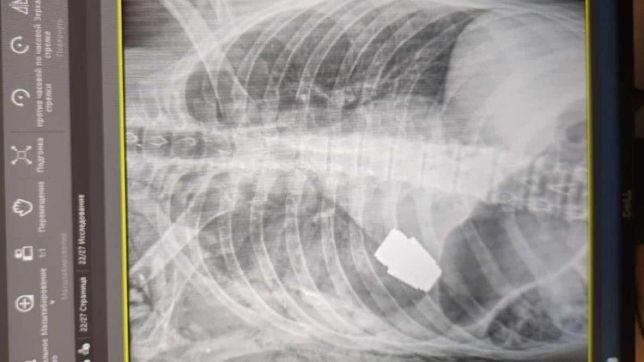

A página oficial do Comando das Forças Médicas das Forças Armadas da Ucrânia no Facebook divulgou detalhes sobre o caso e também compartilhou imagens do raio-X da parte superior do corpo do soldado. A granada no peito era visível pela imagem.